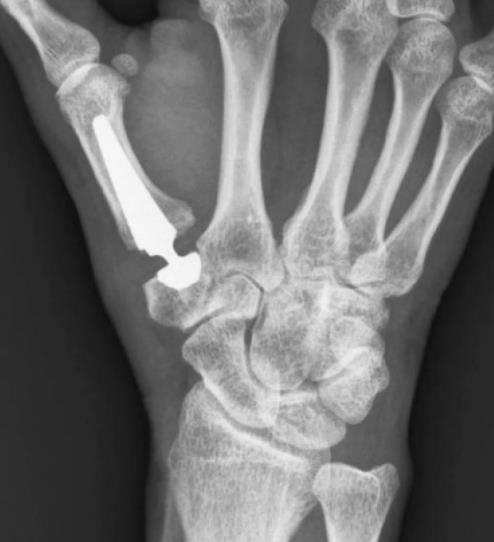

TOUCH® CMC 1 Prosthesis

• The TOUCH® CMC 1 prosthesis is a cementless, dual-mobility ball-and-socket total arthroplasty for the thumb carpometacarpal joint intended for adults with Eaton–Littler stage II–III osteoarthritis after failed nonoperative care

• The device is indicated for primary total replacement of the thumb CMC joint in adults (≥22 years) with symptomatic Eaton–Littler stage II or III osteoarthritis after failure of conservative management

• metacarpal stem made of titanium alloy with titanium plasma-spray and hydroxyapatite coating for press-fit fixation

• trapezial cup made of stainless steel with titanium plasma-spray and hydroxyapatite coating, available in spherical and conical geometries

• modular neck in stainless steel with a cross-linked UHMWPE liner providing dual-mobility articulation

• standard views include frontal and lateral projections with specific hand positioning; the lateral should show MP sesamoids overlapping, and the frontal should not show MP sesamoids while visualizing trapezium-surrounding joint spaces

• CT can be used to assess bone stock and complex morphology